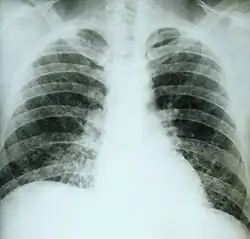

Primary pulmonary histoplasmosis

| This chest film shows diffuse pulmonary infiltration due to acute pulmonary histoplasmosis caused by H. capsulatum. | |

Primary pulmonary histoplasmosis is caused by inhalation of Histoplasma capsulatum spores, and approximately 10% of people with this acute infection develop erythema nodosum.[1]: 316